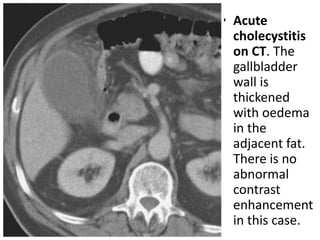

• Acute

cholecystitis

on CT. The

gallbladder

wall is

thickened

with oedema

in the

adjacent fat.

There is no

abnormal

contrast

enhancement

in this case.

• CT isless accurate than US for acute cholecystitis. • The CT findings in acute cholecystitis include gallbladder wall thickening, subserosal oedema, gallbladder distension, high-density bile, pericholecystic fluid and inflammatory stranding in the pericholecystic fat.

• Acute cholecystitis on CT. The gallbladder wall is thickened with oedema in the adjacent fat. There is no abnormal contrast enhancement in this case.